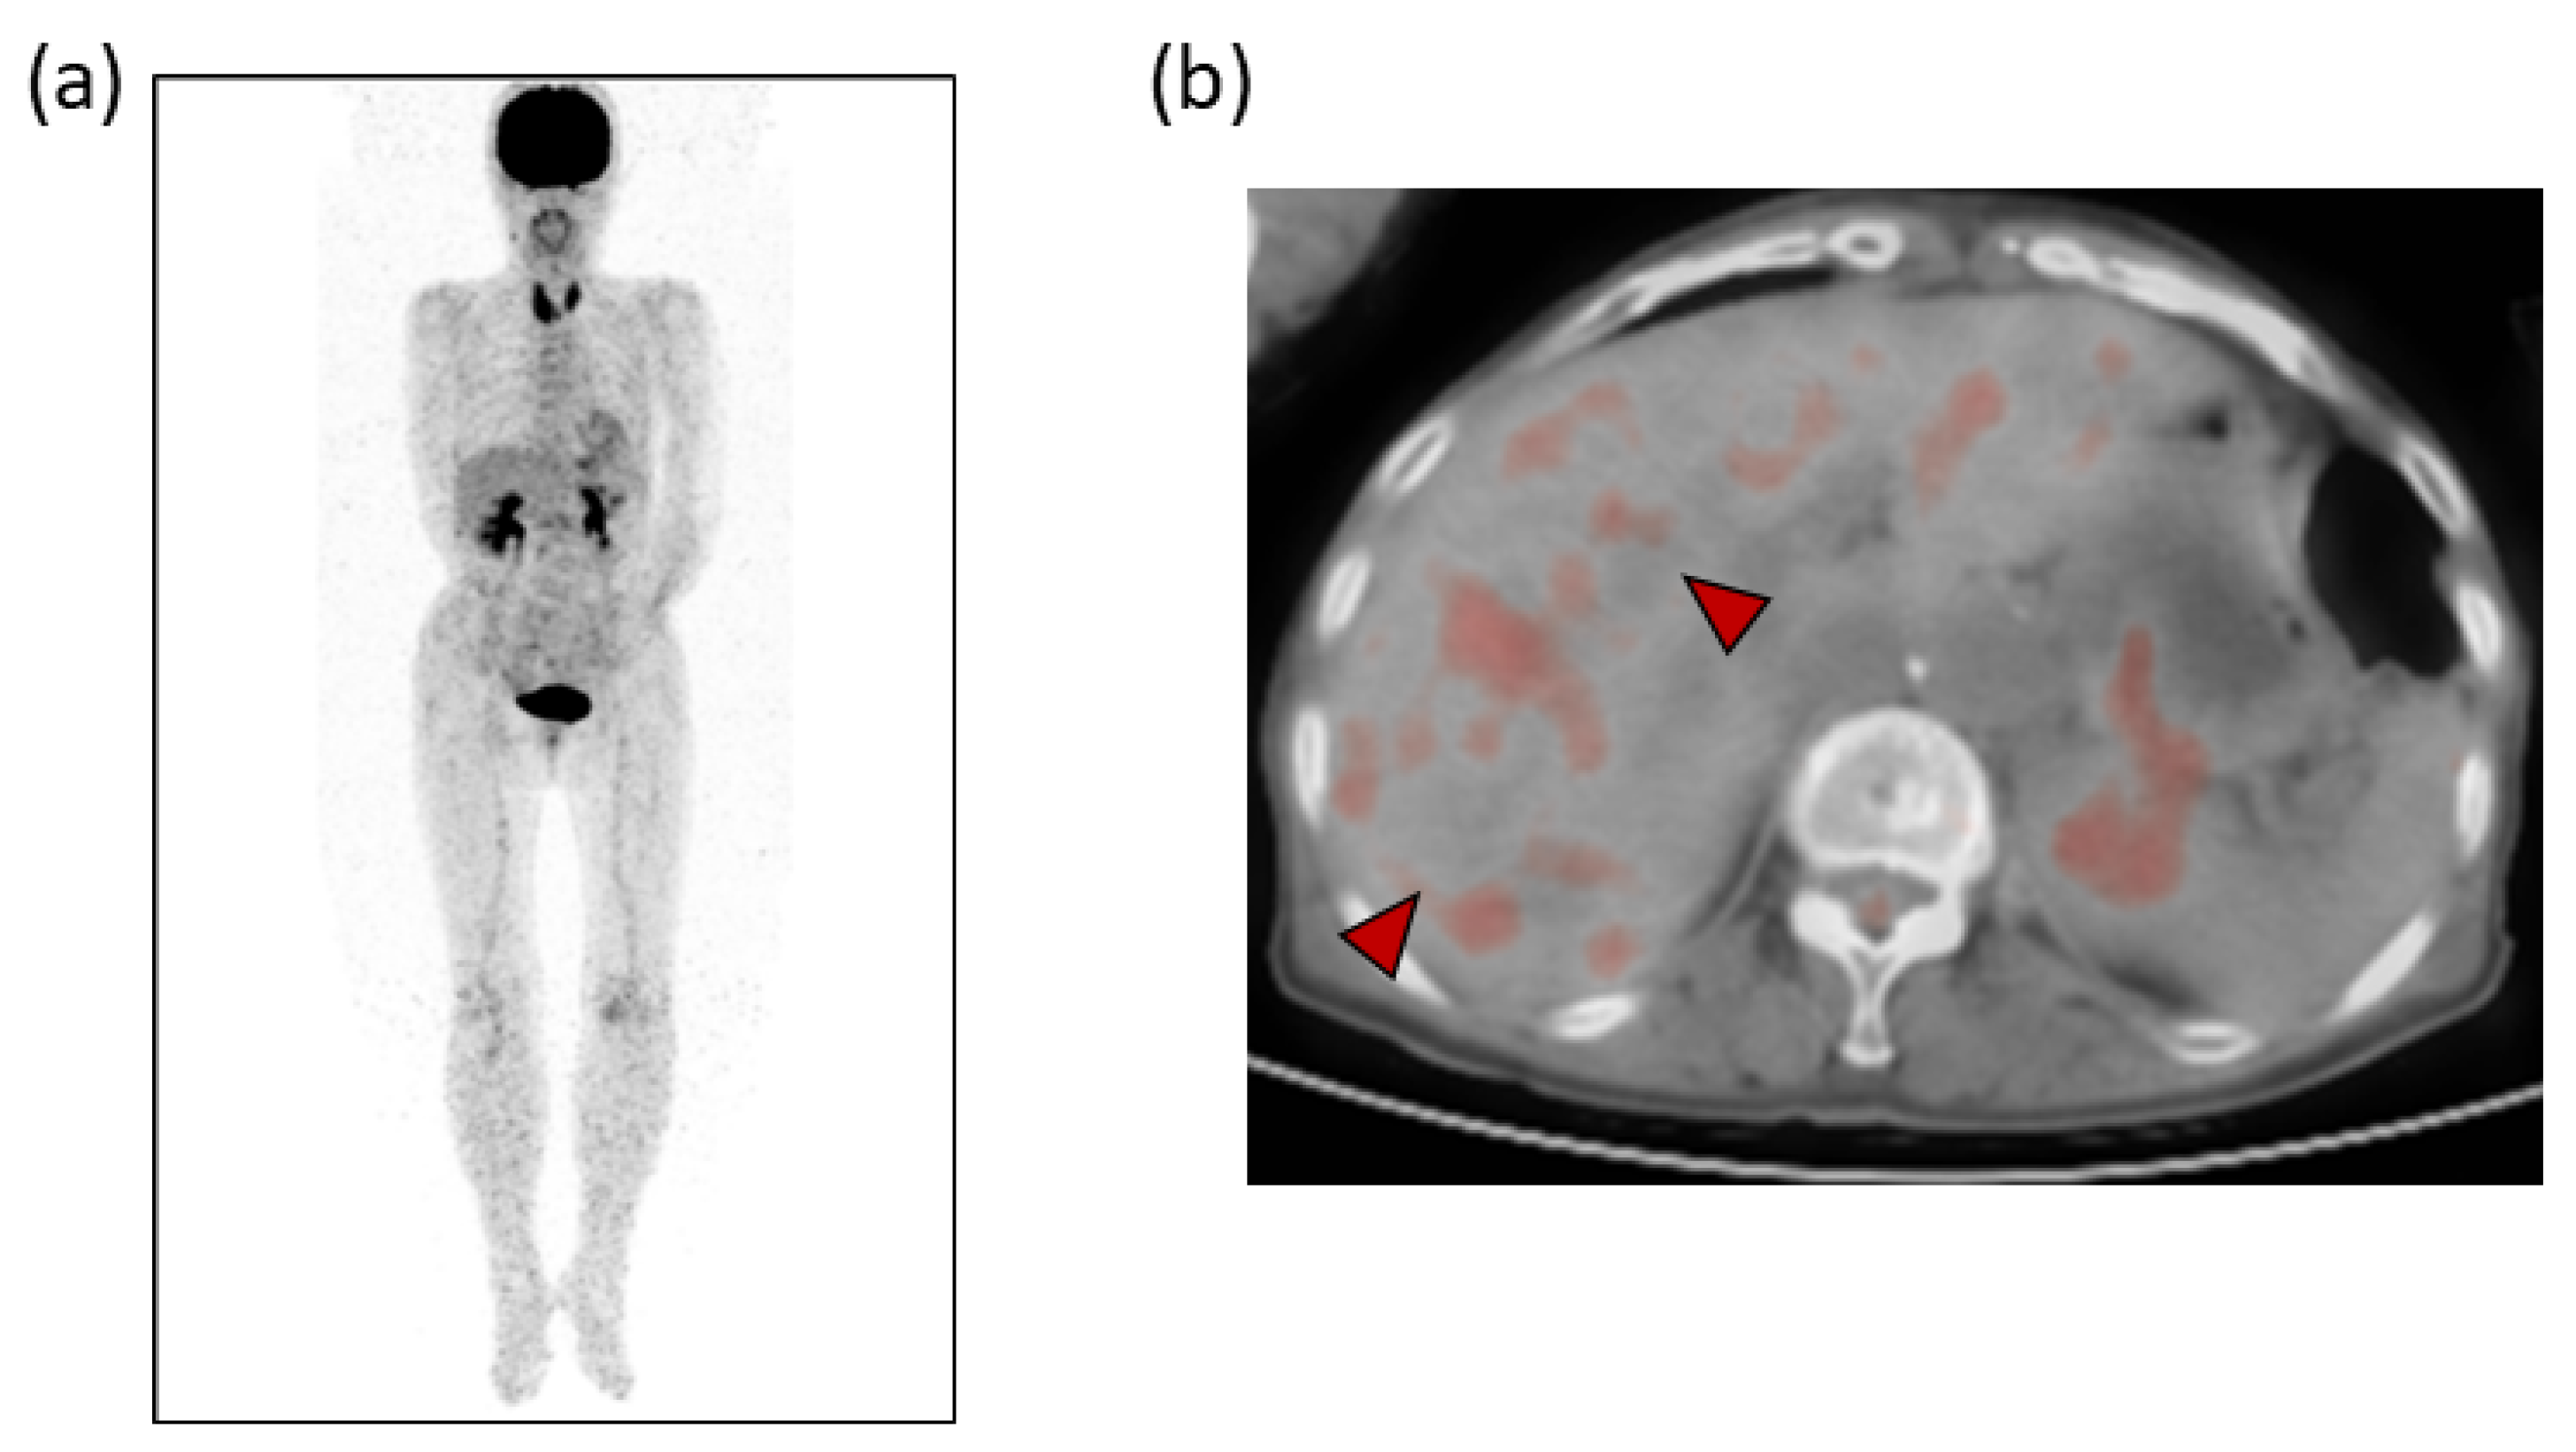

Laboratory examinations (Table 1) showed mild elevation of the serum aspartate aminotransferase and C-reactive protein (CRP) levels. The peripheral blood data, including the white blood cell count and platelet count, and the prothrombin time were found to be within the normal range. Tumor markers, such as carcinoembryonic antigen (CEA), carbohydrate antigen 19-9 (CA19-9), α-fetoprotein (AFP) and protein induced by vitamin K absence or antagonist-II (PIVKA-II), were within the normal ranges. Contrast-enhanced computed tomography (CE-CT) showed low-attenuation areas with mild peripheral enhancement at the arterial and portal phase (Figure 2), suggesting the development of metastatic liver tumors. However, no primary tumor candidate was found on the CE-CT. Esophagogastroduodenoscopy and colonoscopy did not reveal any malignant disease. In addition, despite the presence of suspected metastatic tumors on the US and CT, 18F-fluorodeoxyglucose positron emission tomography with CT (FDG-PET/CT) showed no significant uptake in the tumors (Figure 3).

In our case, CE-CT showed low-attenuation areas in the center of the tumors (Figure 2). However, at the early vascular phase of CEUS, the tumors were shown as very slight hypoenhancement with some hypervascular parts. These CEUS findings were inconsistent with those of metastatic liver tumors, which have internal necrosis. Malignant lesions reportedly show a high intensity on DWI and hypo-values on ADC because of their high cell density [24,25]. Regarding the MRI findings in our case, the DWI showed high-intensity lesions; however, high values were observed on the ADC maps. In addition, the FDG-PET showed a normal standardized uptake value for the tumors. These results were atypical for metastatic tumors.

Despite the presence of findings suggestive of metastatic tumors (Figure 1 and Figure 2), we assessed several different types of clinical data available, such as different imaging techniques, and ultimately concluded that the tumors were benign. Thus, it is quite important to make a diagnosis by combining various imaging findings and considering the patient’s background and clinical course.

Figure 3. (a) 18F-fluorodeoxyglucose positron emission tomography (FDG-PET) and (b) FDG-PET with CT. No apparently significant signal was observed in the tumors (arrowheads).